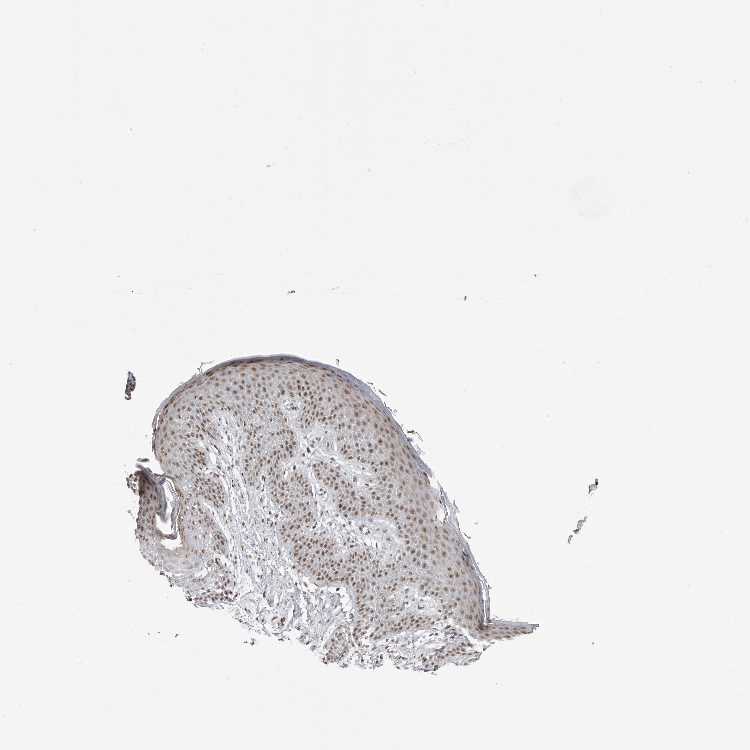

SKIN 1 - Antibody stainingi

Antibody staining in the annotated cell types in the current human tissue is reported as not detected, low, medium, or high, based on conventional immunohistochemistry profiling in selected tissues. This score is based on the combination of the staining intensity and fraction of stained cells.

Each image is clickable and will lead to virtual microscopy that enables deeper exploration of all samples and also displays staining intensity scores, fraction scores and subcellular localization as well as patient and tissue information for each sample.

Antibody HPA023026Antibody HPA028130

Langerhans LowLow

Fibroblasts LowLow

Keratinocytes LowLow

Melanocytes LowLow